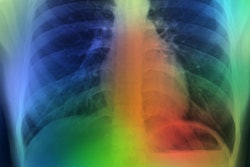

SmartCAD | COVID-19 uses Thirona's CAD4COVID-CT algorithm and Smart Reporting's COVID-19 reporting template to provide direct analysis of chest CT images and then transfers the results into a structured report.

The output includes a COVID-19 severity score on lung and lobar level, the percentage of abnormalities detected for each lobe and the lungs overall, and the percentage of lobar emphysema.